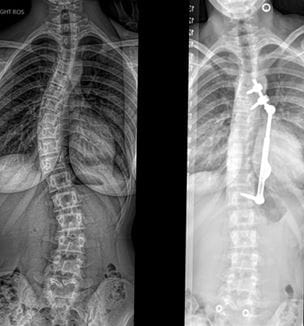

First ApiFix® Procedure Performed at UH Rainbow Babies & Children’s Hospital

Innovations in Orthopaedics | Fall 2021